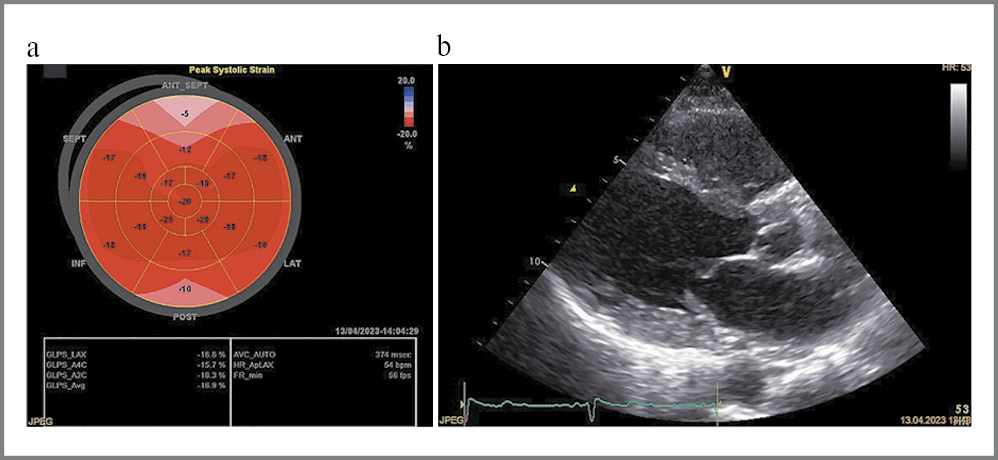

Дополнительное использование технологии спекл-трекинг ЭхоКГ (GLS) позволяет выявить характерную картину в виде снижения продольной деформации базальных и средних сегментов левого желудочка – ЛЖ (бледно-голубой и розовый цвет) с сохраненной деформацией верхушечных сегментов (красный цвет), что является более чувствительным и специфичным признаком АКМП (рис. 1), но сопутствующее нарушение внутрижелудочковой проводимости в виде полной блокады левой ножки пучка Гиса или наличие зон нарушения локальной сократимости могут маскировать типичную картину деформации [11, 12].

Рис. 1. Характерная картина спекл-трекинг ЭхоКГ при АКМП в виде снижения глобальной продольной деформации базальных и средних сегментов ЛЖ (бледно-голубой и розовый цвет) с сохраненной деформацией верхушечных сегментов (красный цвет).

Fig. 1. Typical pattern of echocardiography speckle-tracking in a patient with amyloid cardiomyopathy (ACM) with a decrease in the global longitudinal strain of the basal and middle segments of the LV (pale blue and pink) with preserved strain of the apical segments (red).